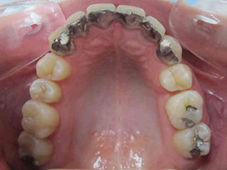

Arcade mandibulaire avant traitement orthodontique, séquelles de maladie parodontale

Arcade maxillaire avant traitement orthodontique, séquelles de maladie parodontale